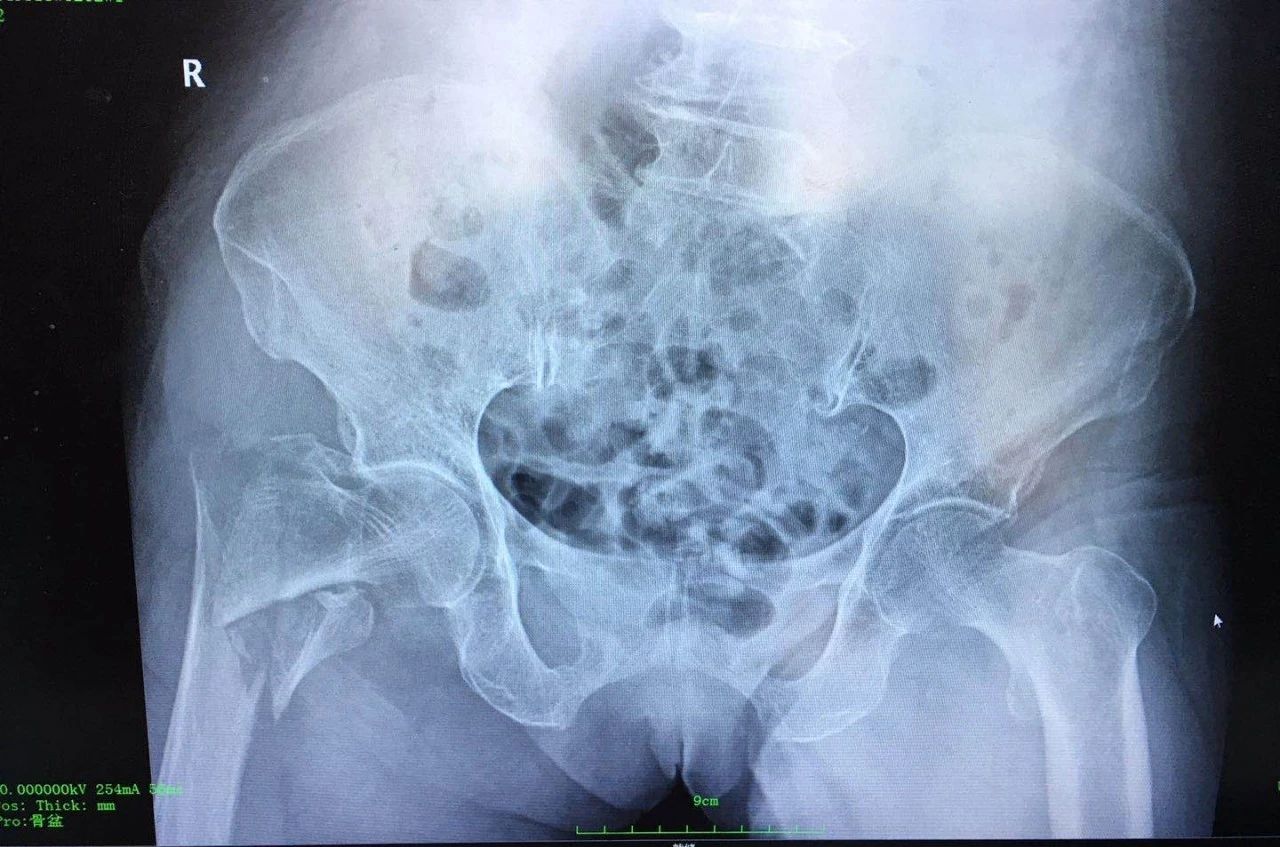

影像资料:

诊 断:

右股骨粗隆间骨折(Evans Ⅳ);右肱骨外科颈骨折术后。